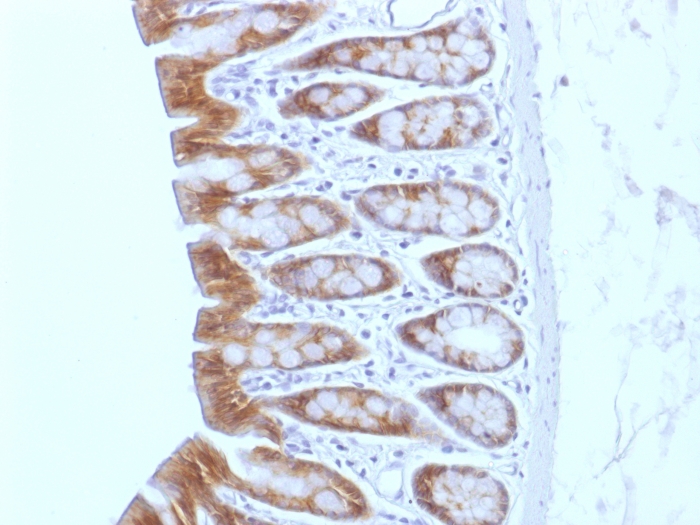

Formalin-fixed, paraffin-embedded Mouse Colon stained with Beta-Catenin (p120) Monoclonal Antibody (CTNNB1/1508).

Beta-catenin associates with the cytoplasmic portion of E-cadherin, which is necessary for the function of E-cadherin as an adhesion molecule. In normal tissues, beta-catenin is localized to the membrane of epithelial cells, consistent with its role in the cell adhesion complex. In breast ductal neoplasia, beta-catenin is usually localized in cellular membranes. However, in lobular neoplasia, a marked redistribution of beta-catenin throughout the cytoplasm results in a diffuse cytoplasmic pattern. Immuno-staining of beta-catenin and E-cadherin is helps in the accurate identification of ductal and lobular neoplasms, including a distinction between low-grade ductal carcinoma in situ (DCIS) and lobular carcinoma. Additionally, some rectal and gastric adenocarcinomas demonstrate diffuse cytoplasmic beta-catenin staining and a lack of membranous staining, mimicking the staining pattern observed with lobular breast carcinomas.